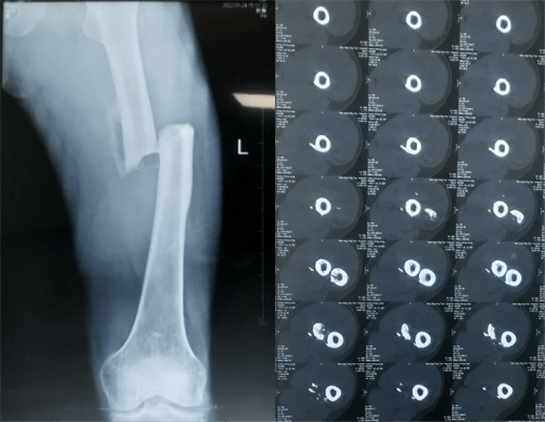

患者:男性,43歲,左股骨干骨折髓內(nèi)釘內(nèi)固定術(shù)

醫(yī)院:南京應(yīng)天骨科醫(yī)院

股骨是下肢的主要負重骨,有其特殊的解剖關(guān)系,周圍肌肉發(fā)達,因此一旦股骨干骨折后如果治療不當,容易造成肌肉牽拉,導致畸形和功能障礙。治療股骨干骨折,必須遵循恢復(fù)肢體的長度及力線,無旋轉(zhuǎn),盡量行以微創(chuàng),保護骨折局部血運,促進愈合。髓內(nèi)釘對骨折的固定能夠達到較大的穩(wěn)定性和堅固性,可以減少醫(yī)源性污染,減少軟組織分離及周圍血供破壞,有利于骨折早期愈合,是治療股骨干骨折的首要治療方法。

術(shù)前檢查